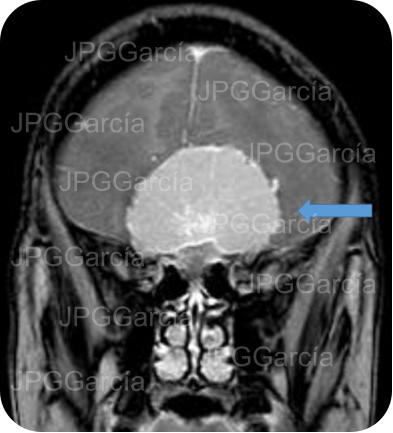

Tumor del plano esfenoidal clasificado por imagen como Meningioma visto a través de resonancia magnética cortes axial y coronal